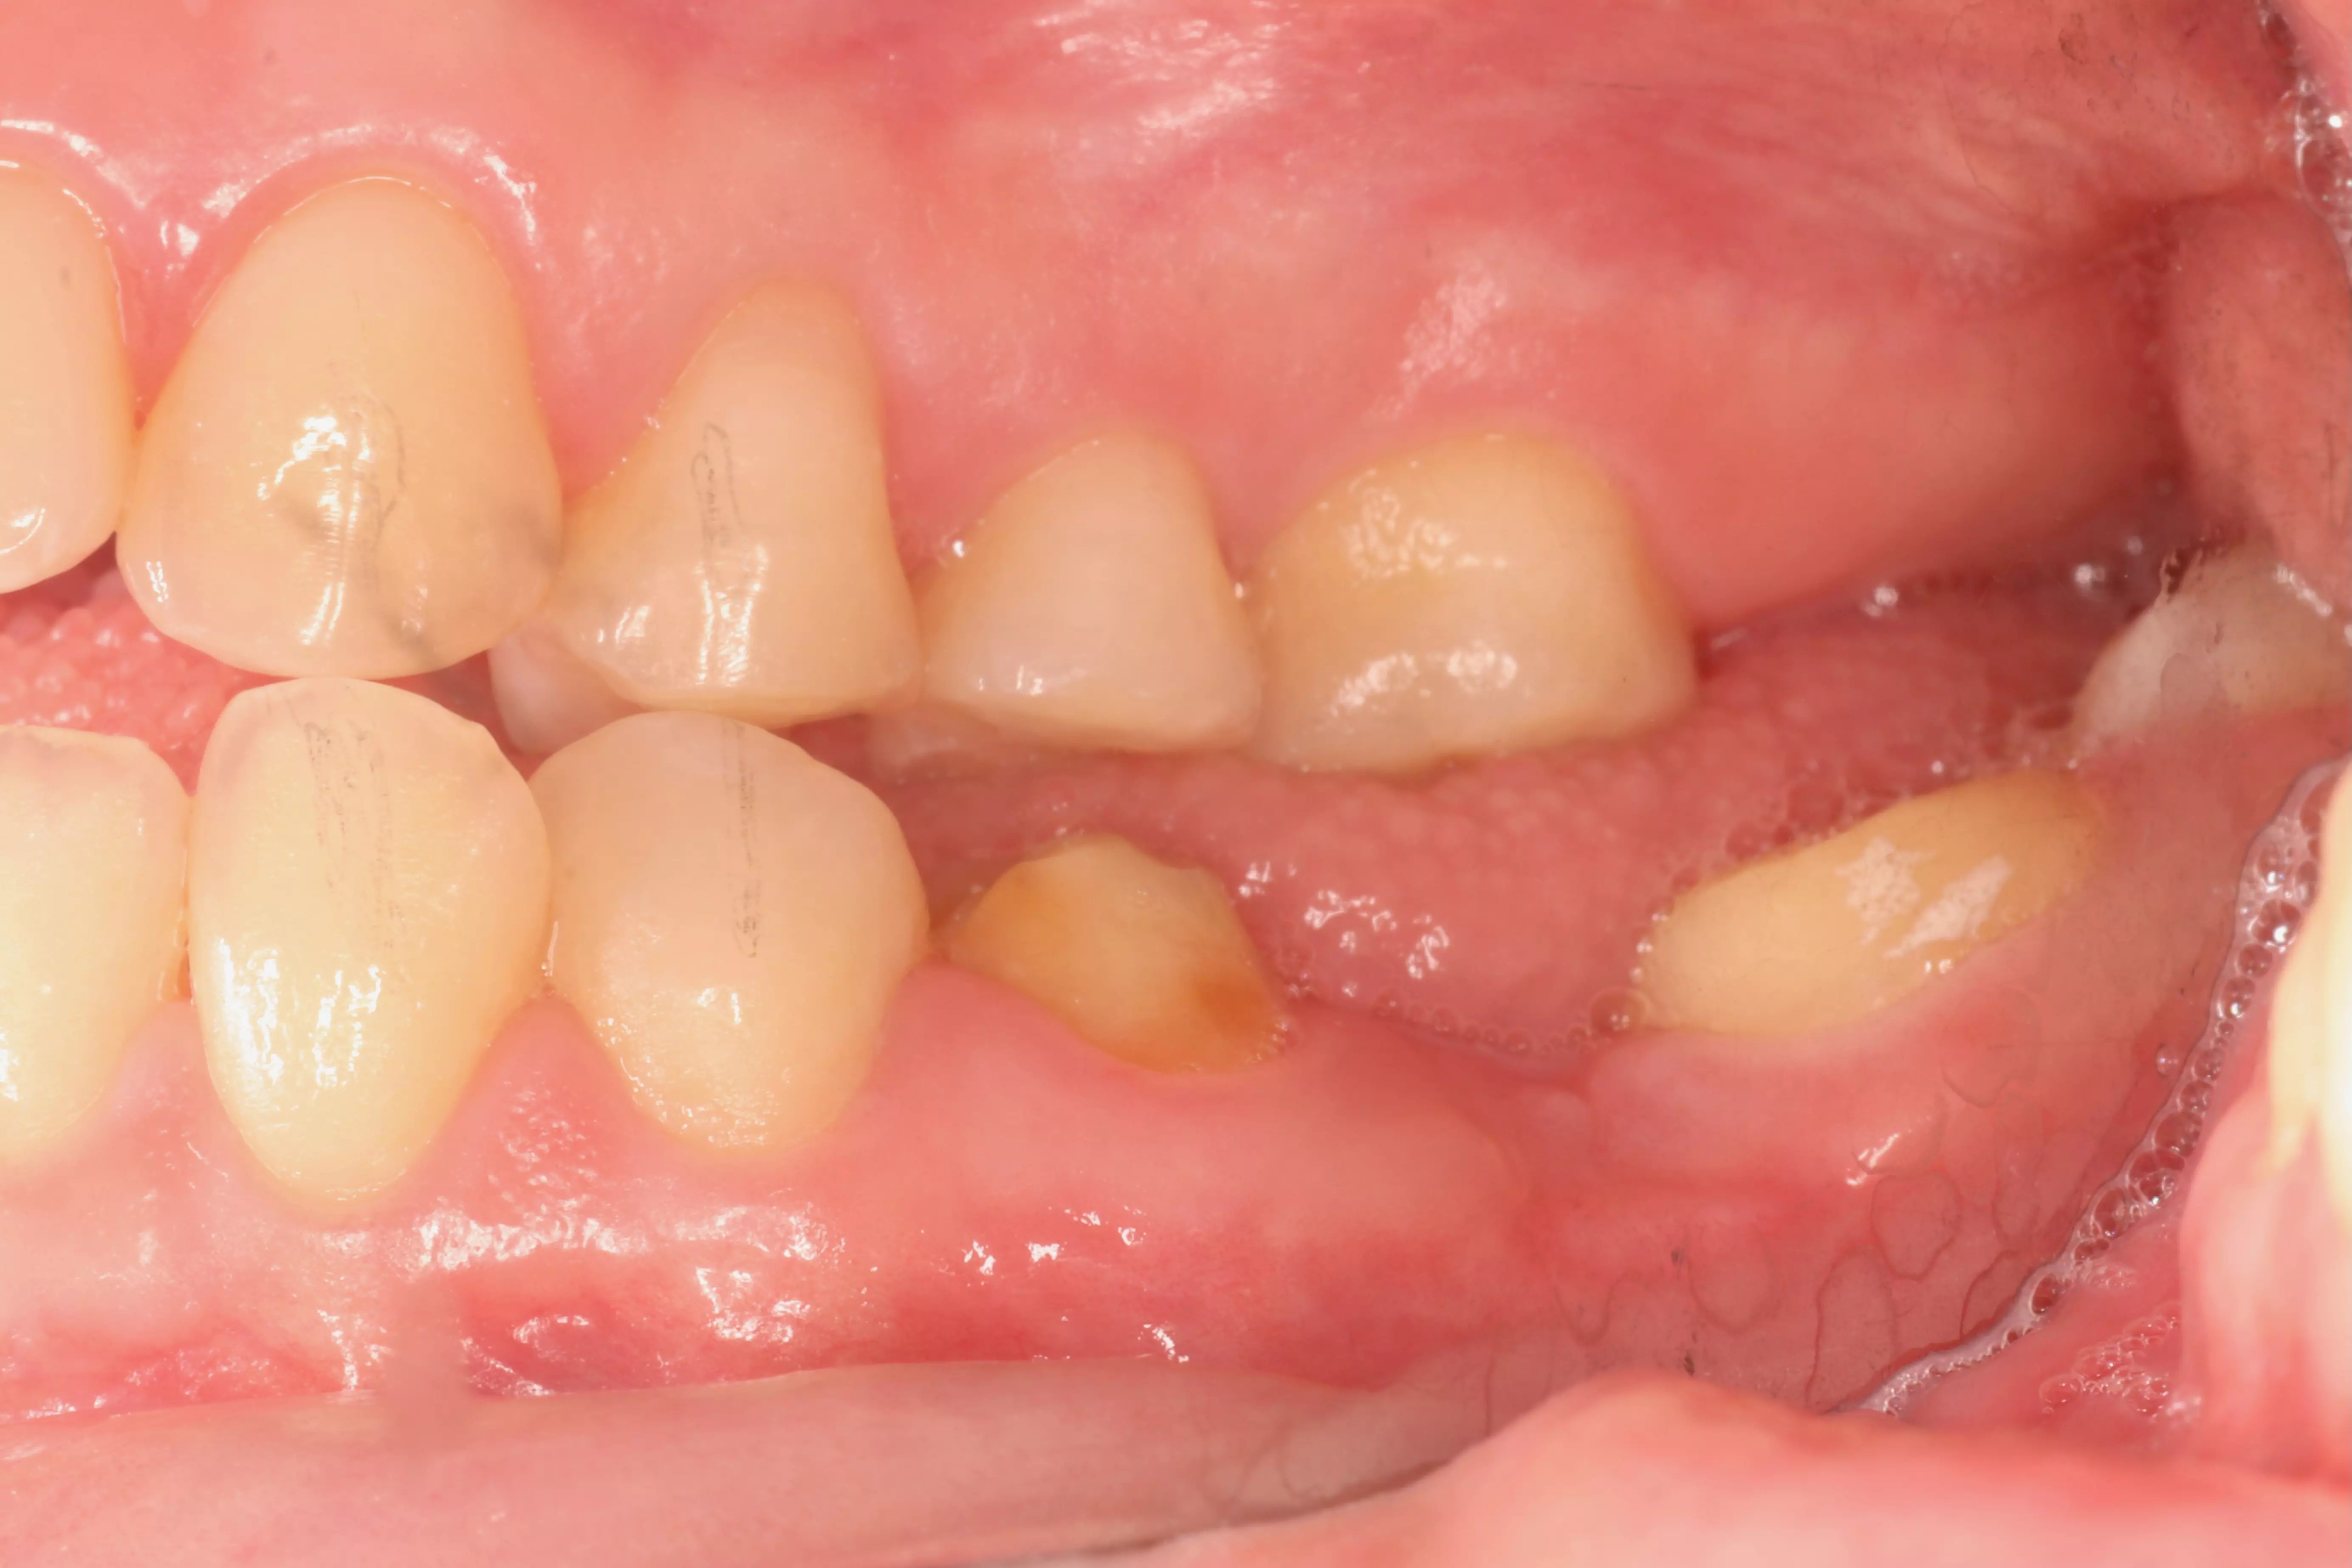

下方是患者初診的照片。患者有嚴重的咬合不正,但是基於身體條件,不適合進行齒顎矯正。下顎左側的缺牙使得她原本就不好的咬合功能變得雪上加霜,吃東西變得更困難。

下方是治療完成的照片。歷時四個多月,在患者、家屬、及醫療團隊的共同努力下,終於完成新的假牙製作。